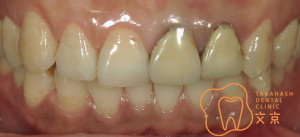

■前歯を治したい 精密審美治療・セラミックス治療

■前歯 精密審美治療

■前歯のセラミックス治療 審美治療

■前歯のオールセラミックス治療

■保険の前歯を直したい